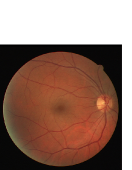

Figure 9: Ground truth (left) and segmentation result (right): (a) and (b) are the images from DRIVE dataset, (c) and (d) are the images from the STARE dataset

V-B Vessel Segmentation Performance

The segmentation performance of the proposed model on three public available datasets is given in Table IV. It can be observed that the proposed model can achieve more than 95%percent9595\% segmentation accuracy on the DRIVE, STARE and CHASE_DB1 datasets, with the highest accuracy score Acc=96.0%𝐴𝑐𝑐percent96.0Acc=96.0\% achieved in the DRIVE dataset. Some exemplary segmentation results are shown in Fig.9. When treating the unknown regions as background regions, AUC=0.833 of trimap is 2.6%percent2.62.6\% lower than the proposed model while Acc of trimap is similar to the proposed model. In addition, Se=0.679𝑆𝑒0.679Se=0.679 of trimap is 5.7%percent5.75.7\% lower than the proposed model. These observations show that trimap can already have good segmentation performance, which indicates that the selection of region features is very effective in segmenting blood vessels. From Table IV, it can be observed that the model with vessel skeleton extraction can achieve more than 5%percent55\% increase of Sensitivity𝑆𝑒𝑛𝑠𝑖𝑡𝑖𝑣𝑖𝑡𝑦Sensitivity and 2%percent22\% increase of AUC𝐴𝑈𝐶AUC compared with the model without vessel skeleton extraction while Acc𝐴𝑐𝑐Acc of the model with vessel skeleton extraction is similar to the model without vessel skeleton extraction, which demonstrates the effectiveness of vessel skeleton extraction.